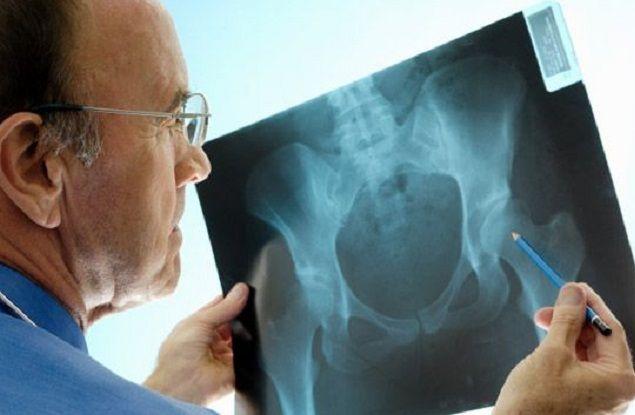

Osteoporosis: En Argentina se producen 90 fracturas de cadera por día

La osteoporosis es una afección generalizada y silenciosa que hace que los huesos sean débiles y frágiles. La enfermedad no tiene síntomas visibles, por lo que muchas personas no saben que la tienen hasta que...